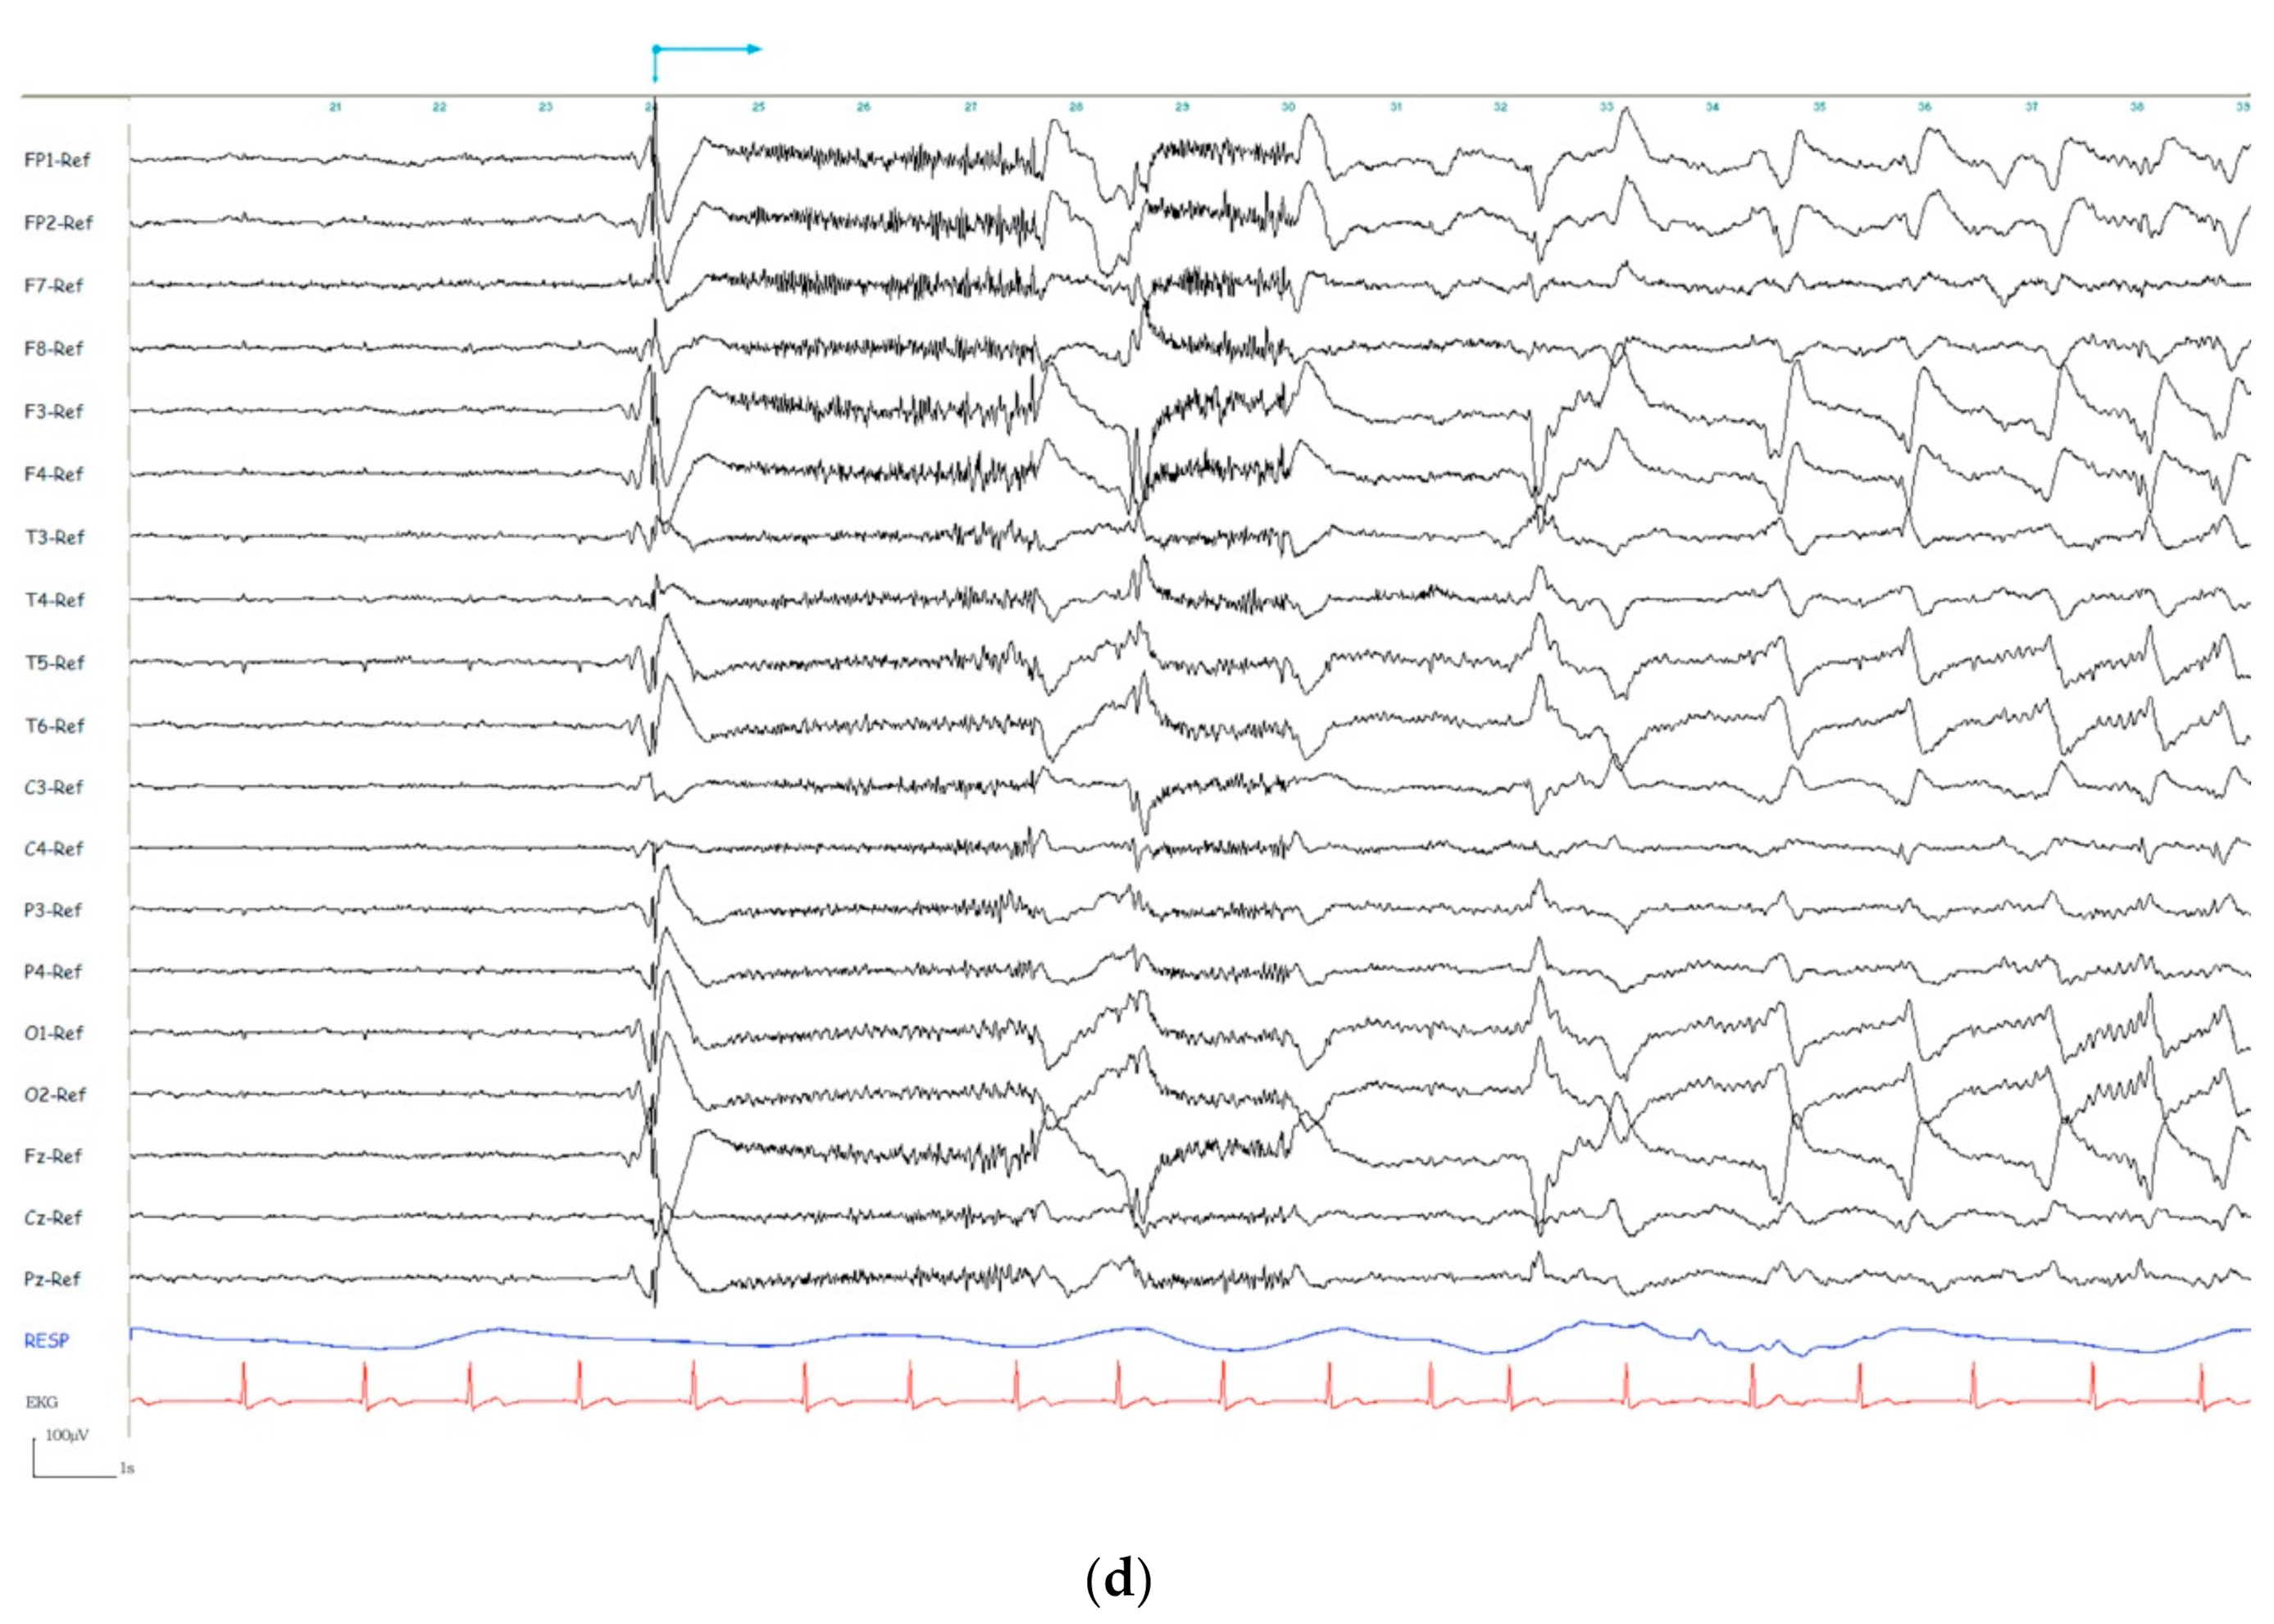

Regarding the seizure onset, four possible EEG categories for seizure onset pattern were observed: rhythmic ictal discharge of >20 µV (Figure 3a), low amplitude ictal beta rhythm (<20 µV) (Figure 3b), global attenuation (<10 µV) (Figure 3c), and IED just prior to the ictal onset (Figure 3d). The term “global attenuation” was used instead of “generalized attenuation” to avoid nomenclature errors in understanding that these seizures were focal and not generalized. For the description of the ictal onset pattern, all the recorded seizures were studied, and it was observed that all could be assigned to one of the four morphological ictal onset patterns. This category was the same for each patient between seizures.

Figure 3.

(a) Seizure onset patterns: Rhythmic ictal discharge of >20 µV. (b) Seizure onset patterns: Low amplitude ictal beta rhythm (<20 µV). (c) Seizure onset patterns: Global attenuation (<10 µV). (d) Seizure onset patterns: Interictal epileptiform discharge (IED) just prior to the ictal onset.

Regarding the seizure onset, four possible EEG categories for seizure onset pattern were observed: rhythmic ictal discharge of >20 µV, low amplitude ictal beta rhythm (<20 µV), global attenuation (<10 µV), and IED just prior to the ictal onset accounting for 41.17%, 27.45%, 19.60% and 11.76%, respectively, in our series. Frontal lobe seizures are a diagnostic challenge, especially due to the short duration, the low amplitude seizure onset, and the subtle semiology of some frontal seizures.